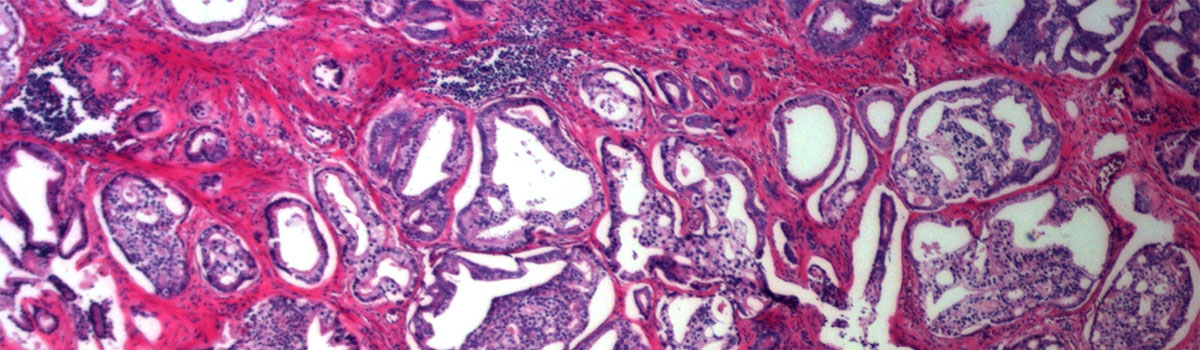

Microscopic image of biopsy

The view through a microscope of a 100% prostate cancer biopsy.